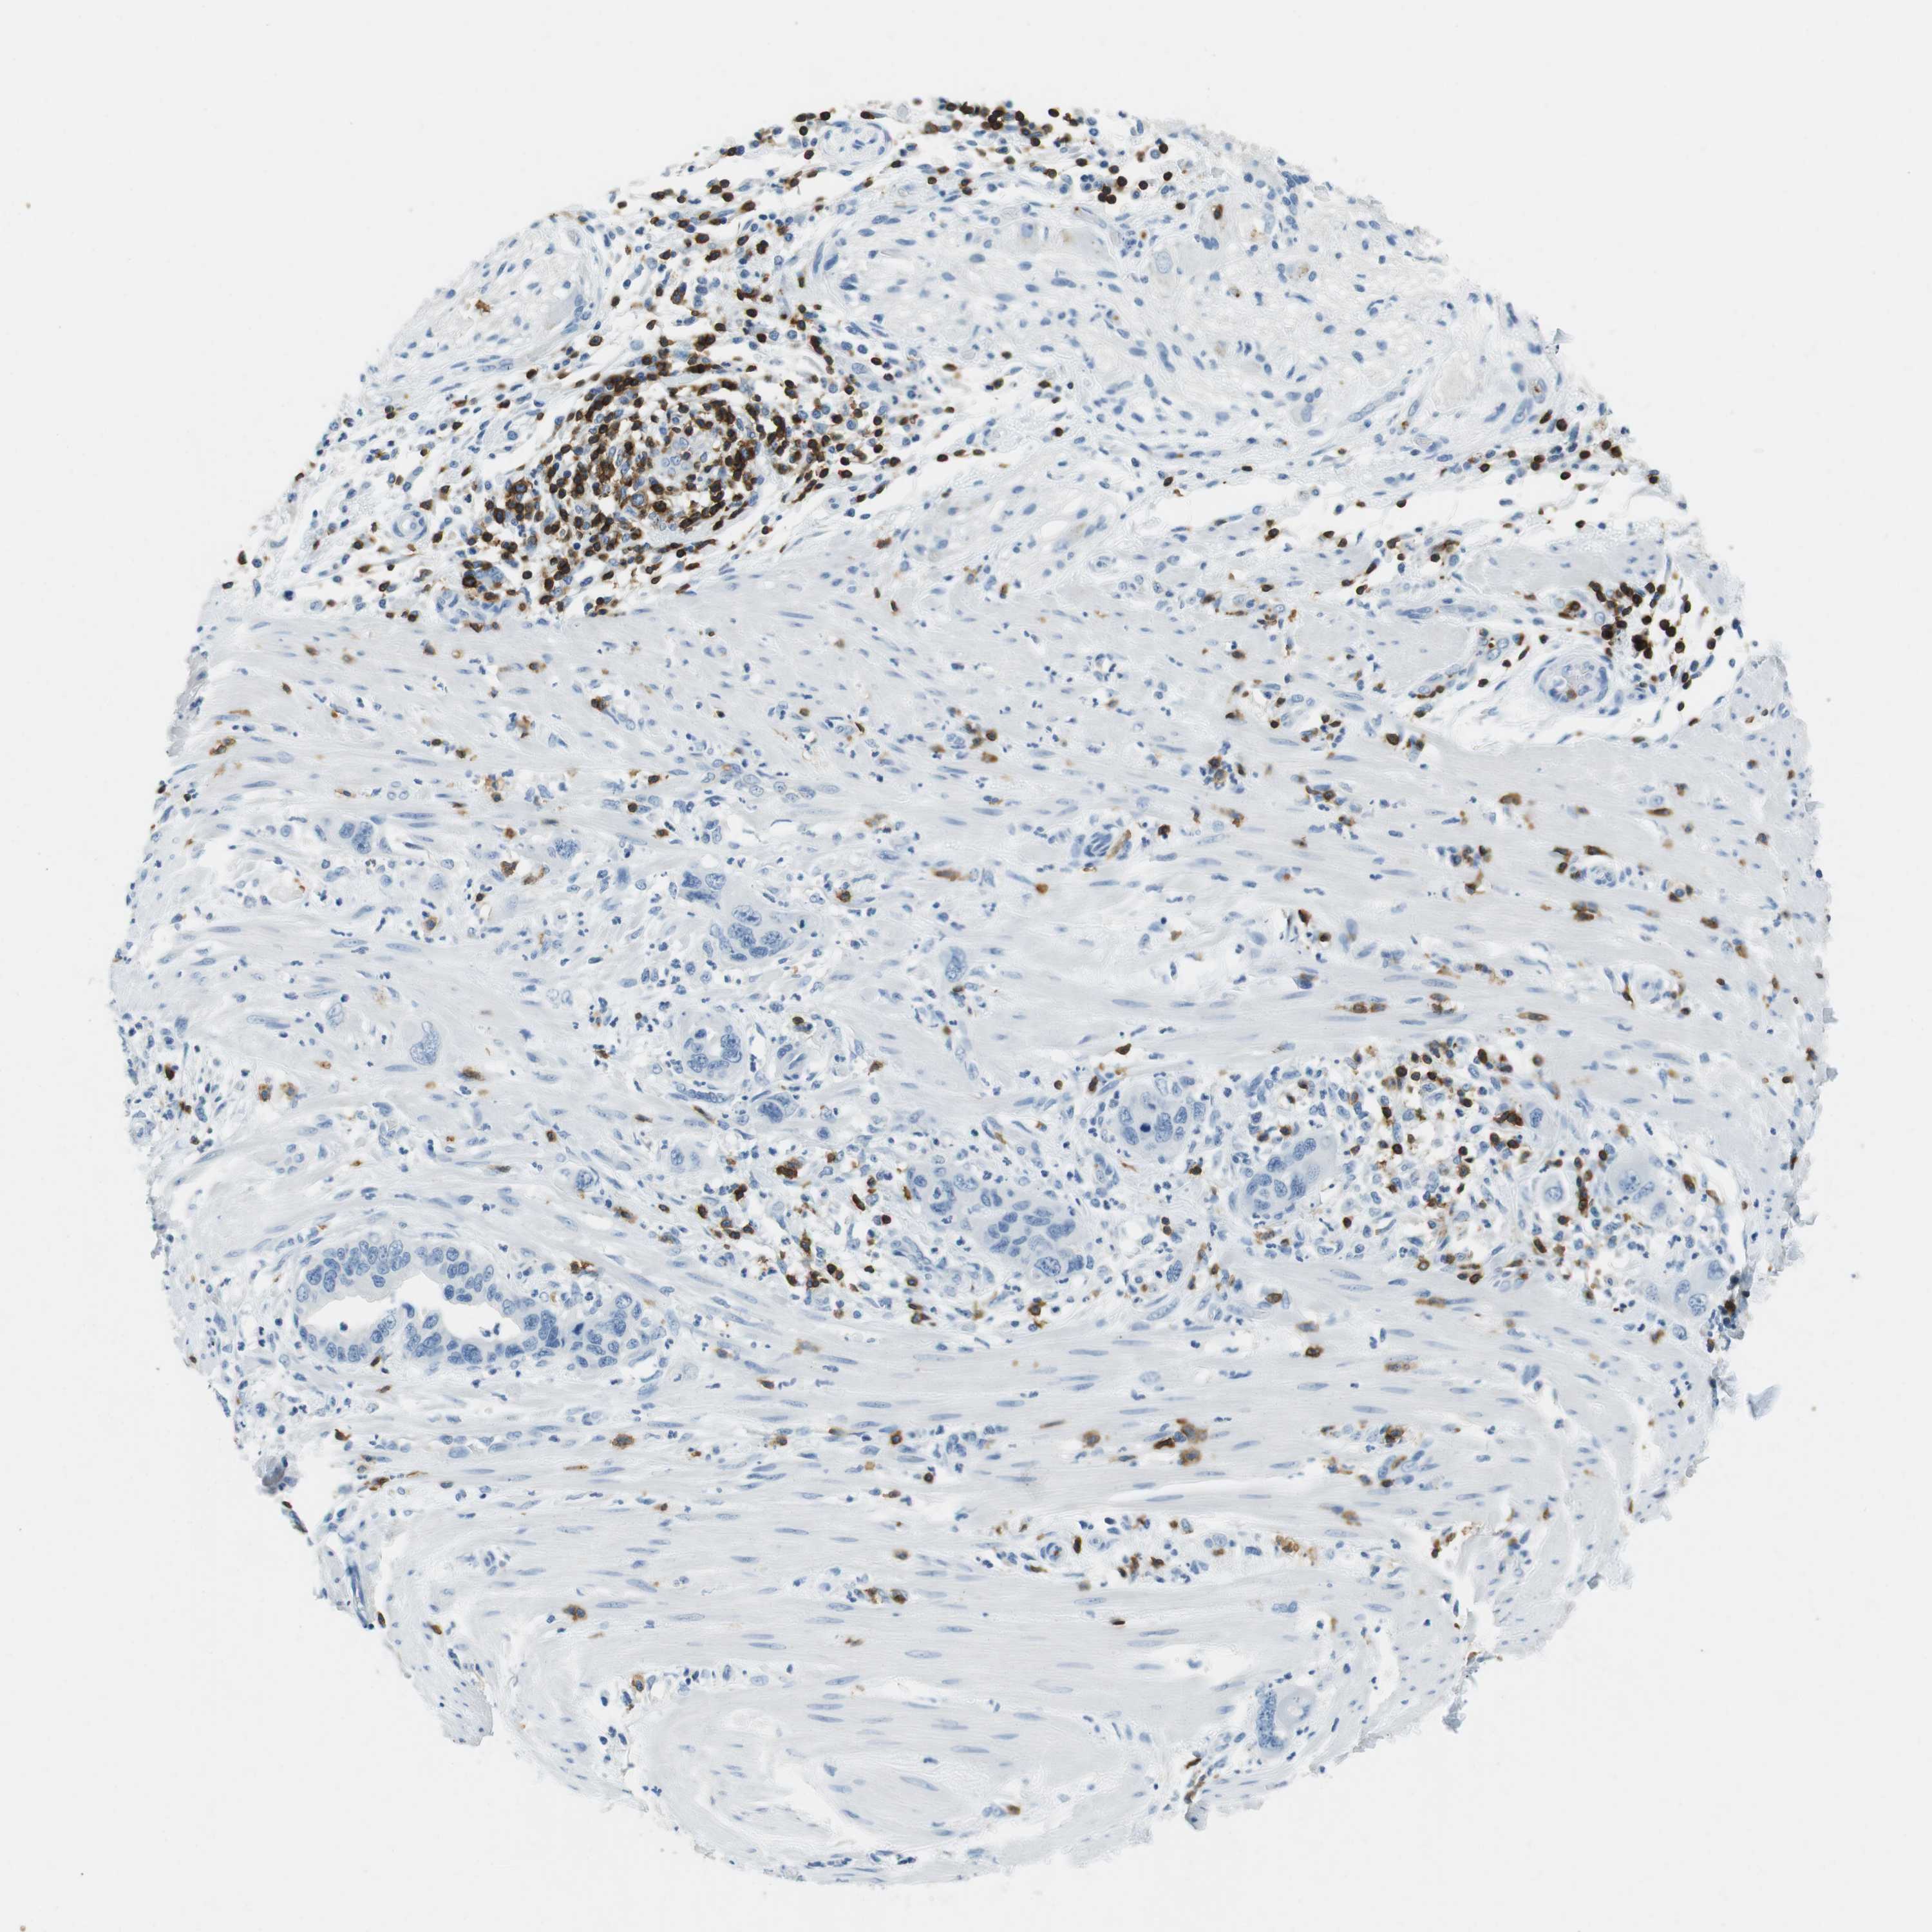

PANCREATIC CANCER - Protein expressioni

A mouse-over function shows sample information and annotation data. Click on an image to view it in a full screen mode. Samples can be filtered based on level of antibody staining by selecting one or several of the following categories: high, medium, low and not detected. The assay and annotation is described here.

Note that samples used for immunohistochemistry by the Human Protein Atlas do not correspond to samples in the TCGA dataset.

Antibody stainingi

Antibody staining in the annotated cell types in the current human tissue is reported as not detected, low, medium, or high, based on conventional immunohistochemistry profiling in selected tissues. This score is based on the combination of the staining intensity and fraction of stained cells.

Each image is clickable and will lead to virtual microscopy that enables deeper exploration of all samples and also displays staining intensity scores, fraction scores and subcellular localization as well as patient and tissue information for each sample.

Antibody HPA011157

Antibody CAB002223

Antibody CAB012978

Antibody CAB079960

Staining

High

Medium

Low

Not detected

Intensity

Strong

Moderate

Weak

Negative

Quantity

>75%

75%-25%

<25%

None

Location

Nuclear

Cytoplasmic/membranous

Cytoplasmic/membranous,nuclear

Adenocarcinoma, NOS

Adenocarcinoma, metastatic, NOS